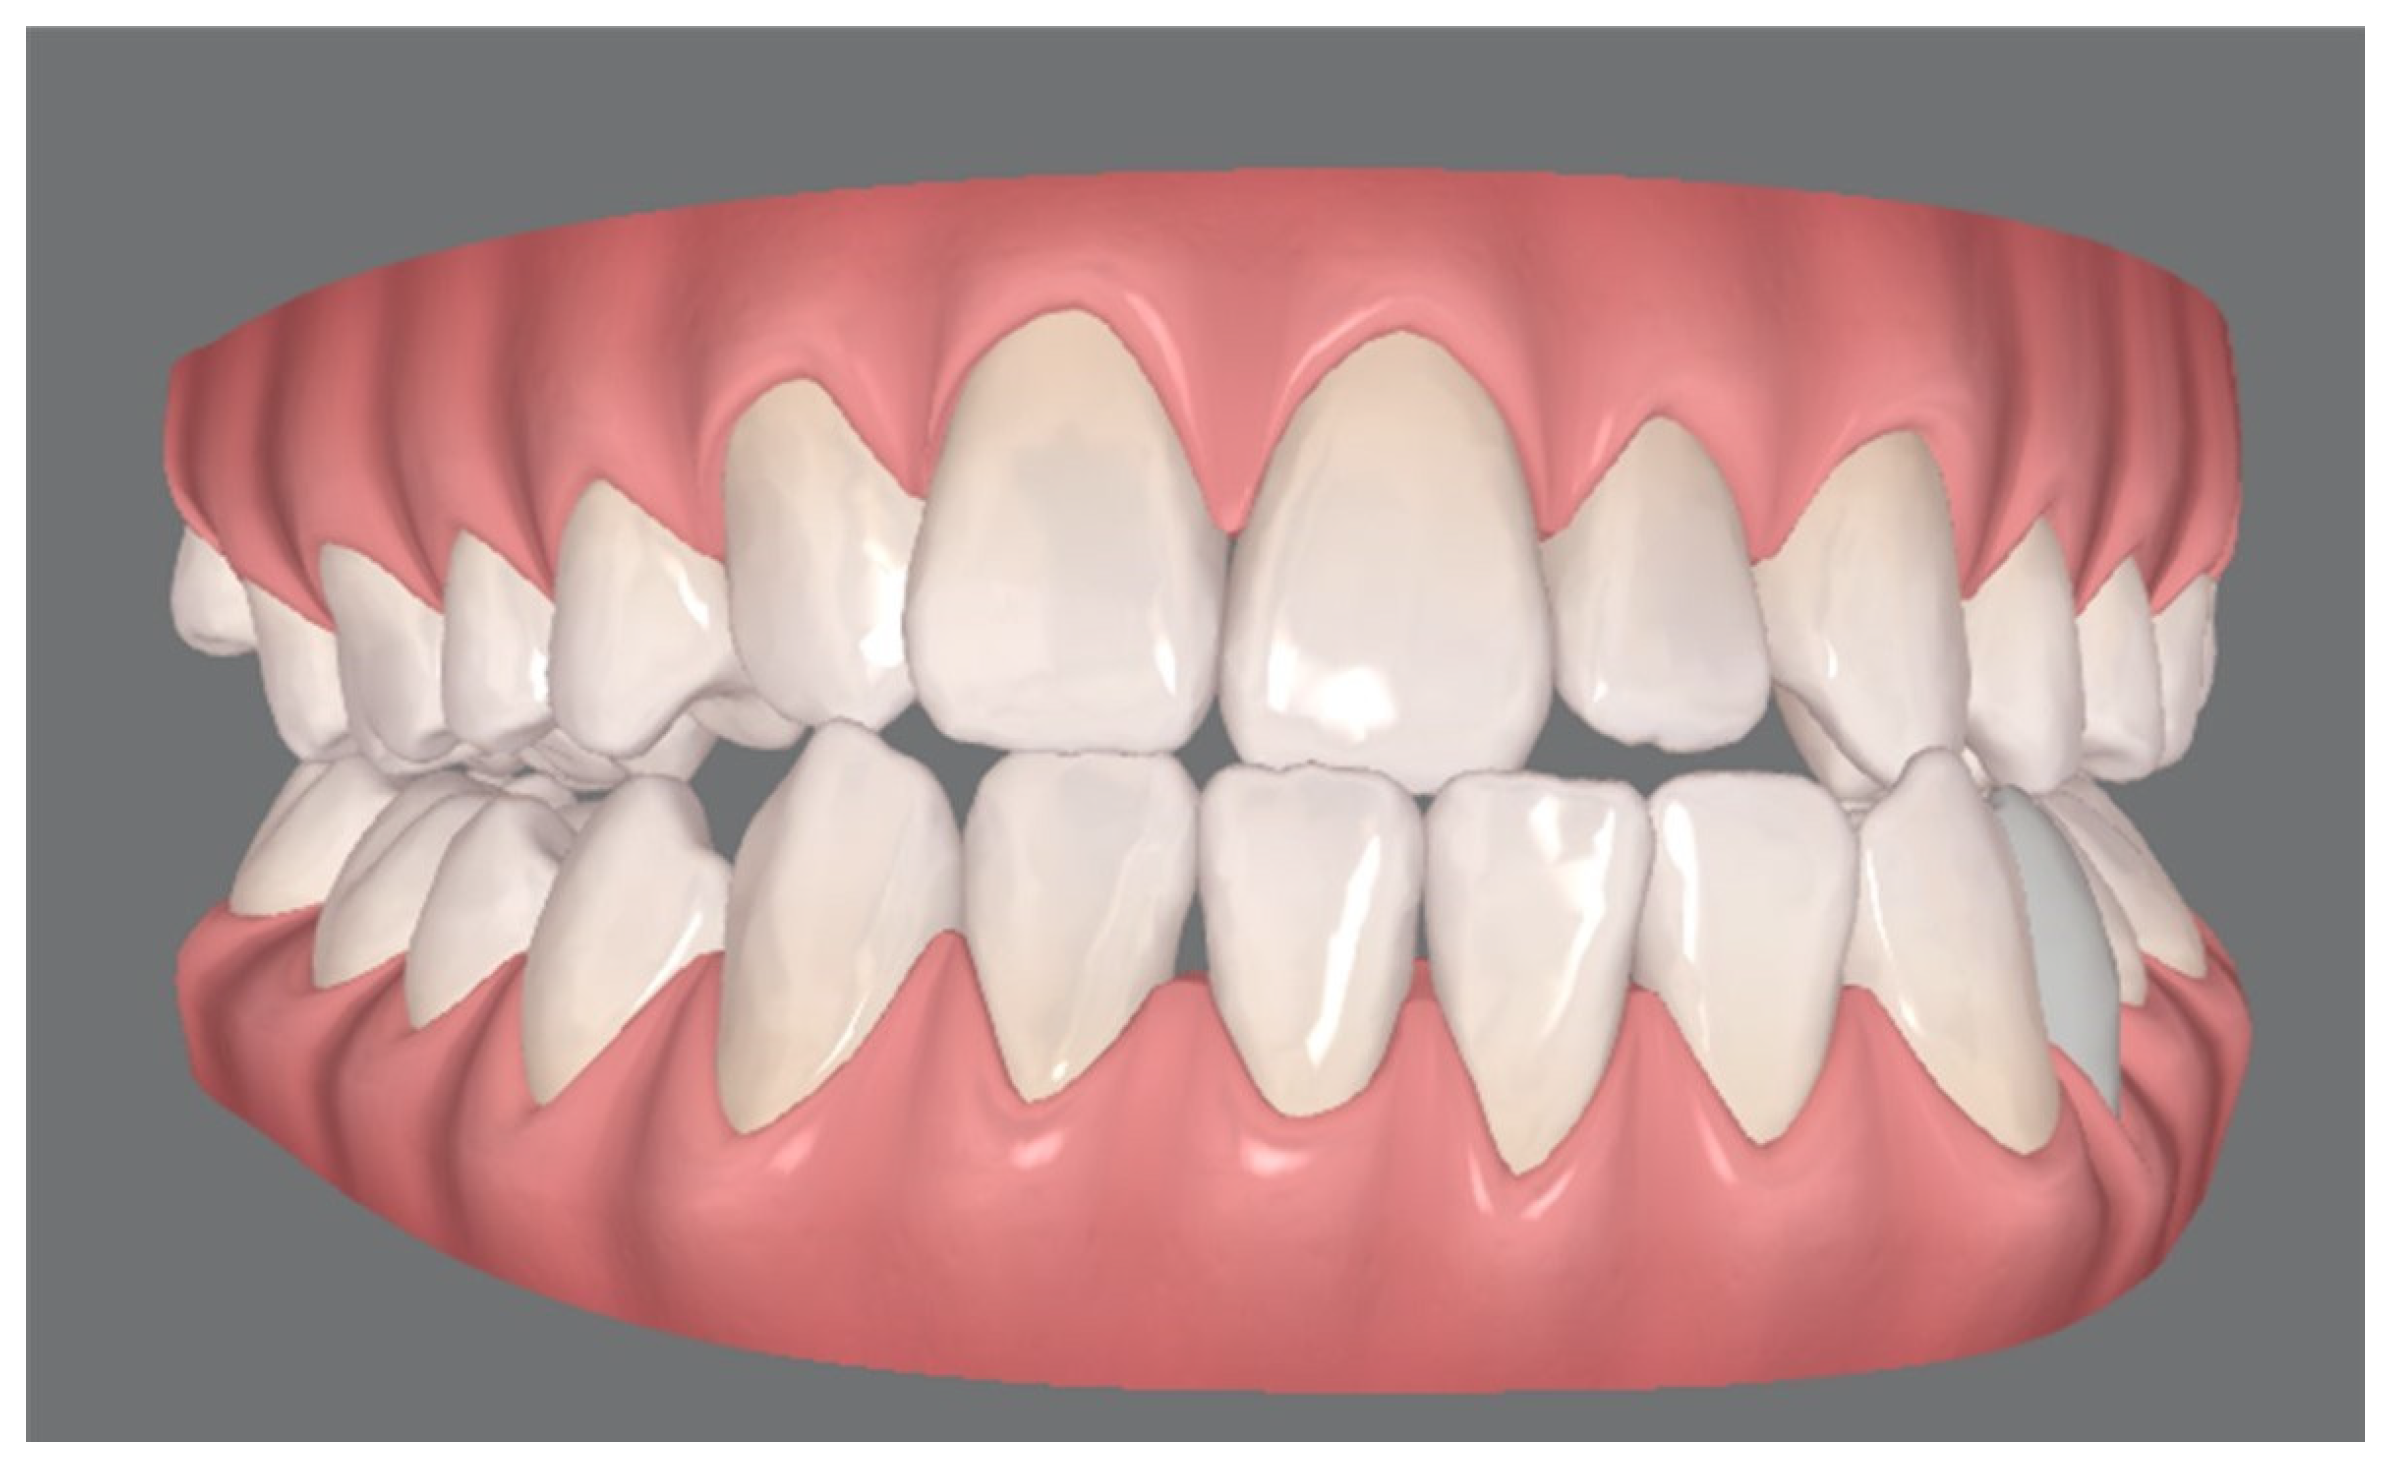

Pre-Surgical Orthodontic Treatment

- Clear aligner technique